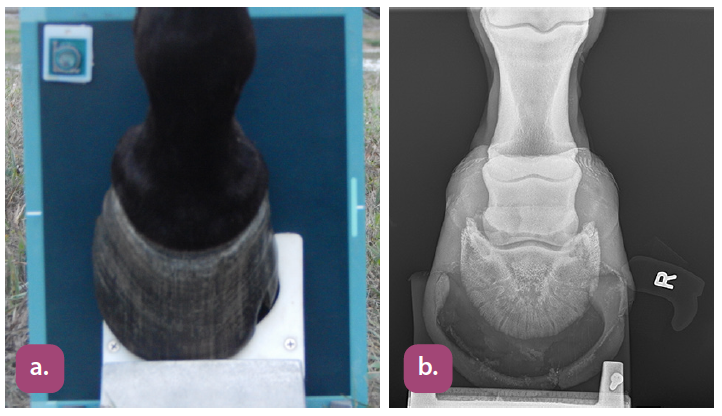

45 degree dorsopalmar coffin bone projection

skyline (palmar proximal) navicular projection